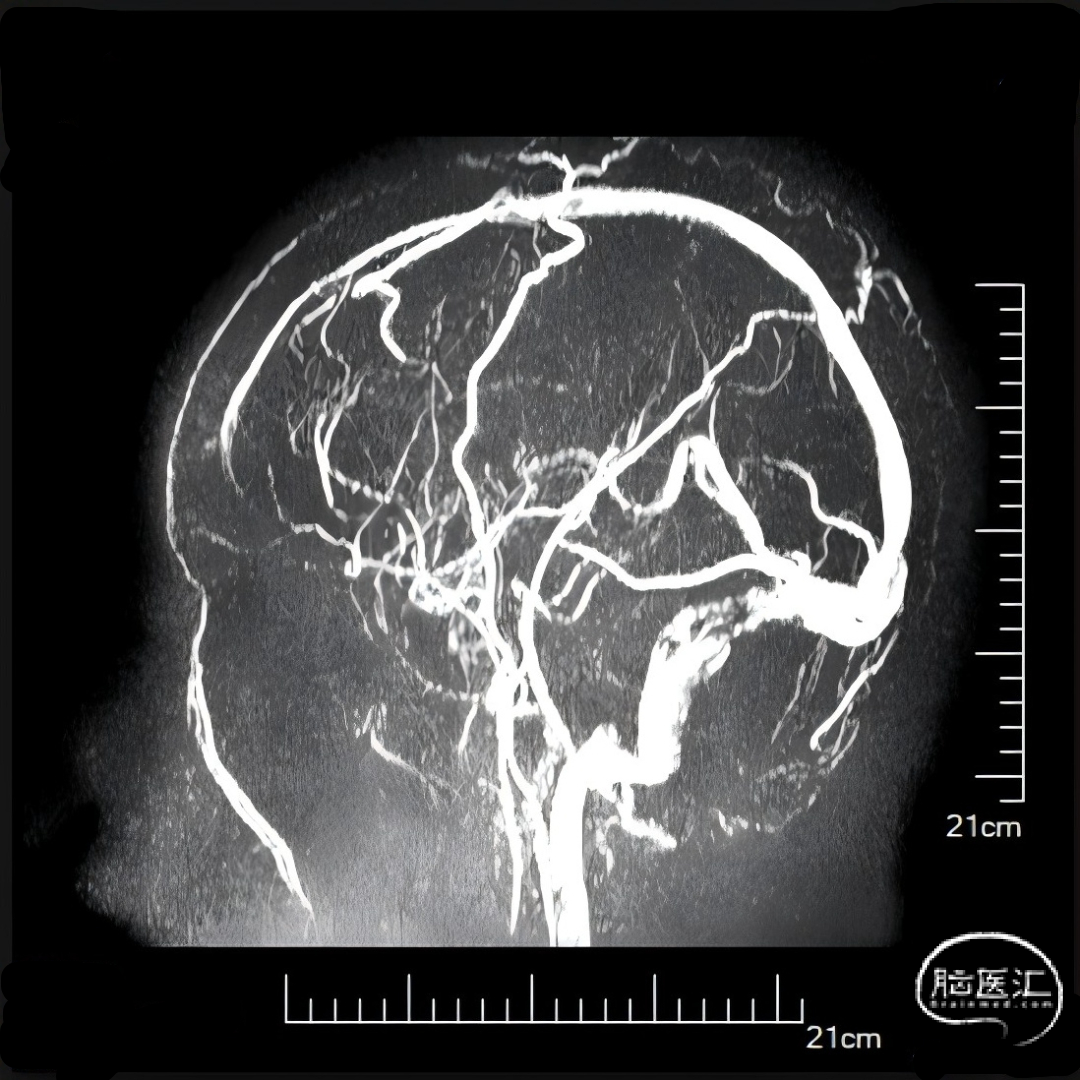

股动脉穿刺置5F鞘做静脉窦造影,股静脉穿刺置8F鞘进行治疗。260cm泥鳅导丝,将132cm 0.068" React™导管送至上矢状窦前部,尽量推高长鞘,增加支撑力。

经中间管手推造影,确认血栓位置。

单纯抽吸难以实现良好再通,经300cm微导丝长交换送入115cm Navien™颅内支撑导管;选用5*30mm球囊扩张,碎栓。

球扩后造影,上矢状窦接触溶栓尿激酶20万U。

球囊扩张和接触溶栓后,再次经中间管反复抽吸后复查造影。

再次给予尿激酶10万U后复查造影。

再次给予球囊扩张,球扩后复查造影。